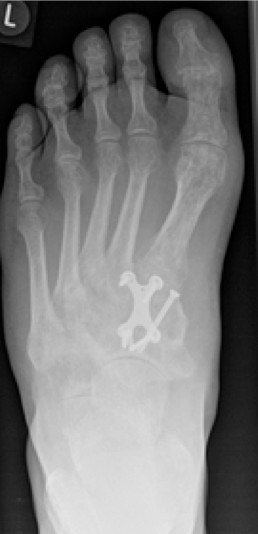

2.-Postoperatives Bild Februar 2017

Im Rahmen einer Verlaufskontrolle zeigte sich ein Schraubenbruch als Zeichen einer fehlenden Durchbauung der Arthrodese.

3.- April 2017: Schraubenbruch

Bei einer Verlaufskontrolle im Juli 2017 ergab sich bei der Röntgenuntersuchung eine Fehllage einer Plattenschraube, die damit das TMT 2 überbrückte.

5.- 07/2017 Schraubenfehllage : Schraube erreicht Basis MT2 und überbrückt TMT 2

Im CT vom September 2017 ergab sich noch kein Durchbau der Arthrodesen, aber ein Bruch der das TMT 2 überbrückenden Schraube.

6.- 09/2017 Schraubenbruch